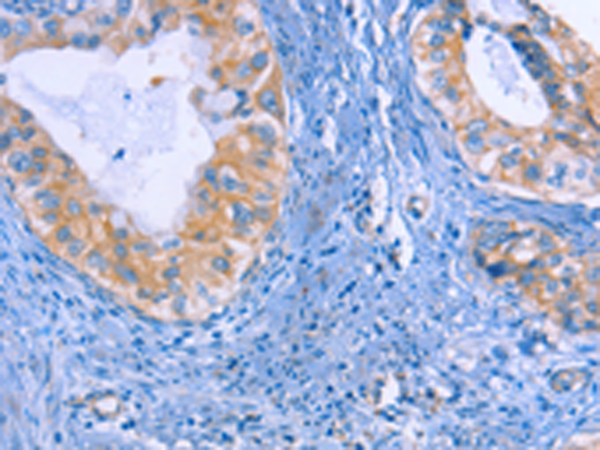

分类: 科研抗体货号: P00534别名: MI; WS2; CMM8; WS2A; COMMAD; bHLHe32应用: WB,IHC反应种属: Human, Mouse, Rat